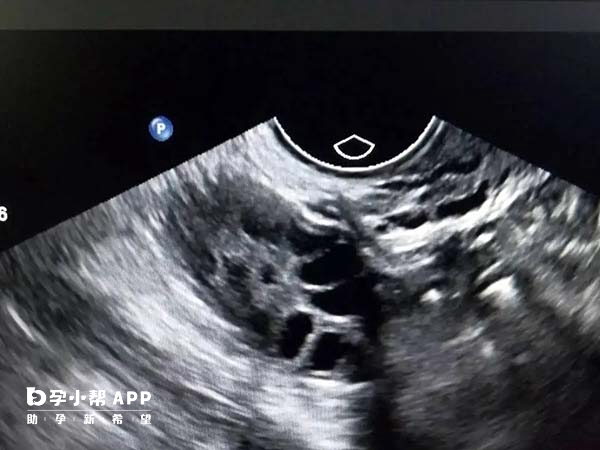

優質卵子是試管嬰兒成功的前提之一,如果患者使用的是自然週期移植方案,那麼一般不需要使用藥物來調整經期,這樣雖然能降低過度刺激卵巢的風險,但是不利於醫生控制卵泡發育速度,從而無法準確判斷打夜針、取卵或移植時機,所以患者需要經常去醫院監測卵泡,以便醫生及時瞭解卵泡的發育情況、成熟程度和功能狀態,為下一步提前作出部署。

一般來說,正在促排卵或準備進行凍胚移植的患者都需要監測卵泡,一如果在試管嬰兒卵泡監測過程中,未遵醫囑按時複診檢查,可能會影響試管成功率,從而延長試管週期,為方便大家瞭解在試管嬰兒中卵泡監測的重要性,下面簡要列舉了幾點: